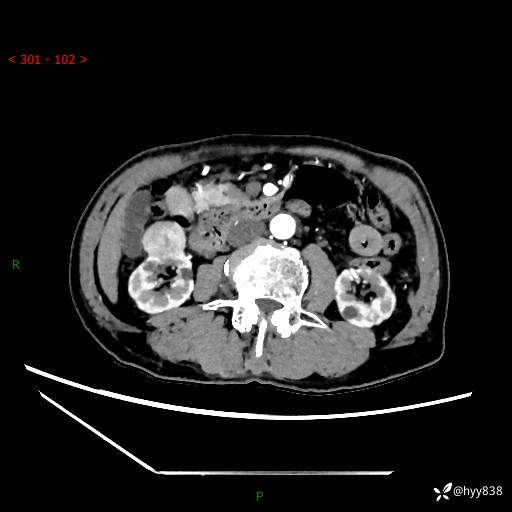

辅助检查:CT

肾脏CT平扫

增强(皮质期+髓质期+排泄期)

三期CT值:132hu 107hu 81hu